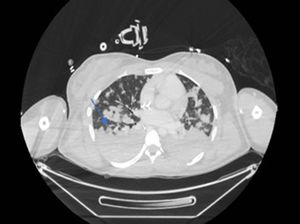

De forma paulatina la paciente va estabilizándose tanto desde el punto de vista respiratorio como del hemodinámico, permitiendo trasladarla para realizar estudio de extensión con tomografía axial computarizada (TAC), en el que se aprecian múltiples abscesos pulmonares (fig. 1), dos abscesos hepáticos e infarto esplénico (fig. 2)1; cráneo sin hallazgos.